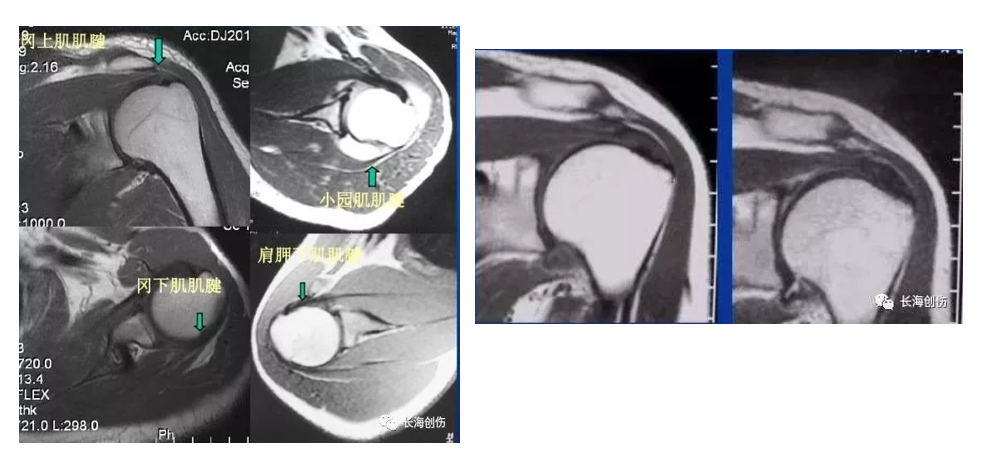

核磁共振:MRI不但可以显示肩袖损伤的程度、范围、肌腱回缩、脂肪浸润和肌肉萎缩等情况,还可以显示肱二头肌长头腱、肩峰形态、肩峰下间隙、肩锁关节等更多的信息。

MRI 分级:0 级:正常的肩袖韧带在MRI上为均匀的低信号,是肌腱的延续;1 级:又称肌腱炎,这时肩袖的连续性是完整的,但是在冈上肌肌腱内见信号的增高。1 级的信号改变在质子加权图像中显示最为清晰,为中等信号。这种信号的改变最为可能是由于水肿、炎症反应和出血所引起的;2 级:T1WI或PDWI上见有信号增高并见肩袖的变细或不规则,滑囊内通常有积液;3 级:T2WI上信号增高涉及整个肌腱,肌腱连续性中断,滑囊内多有积液。